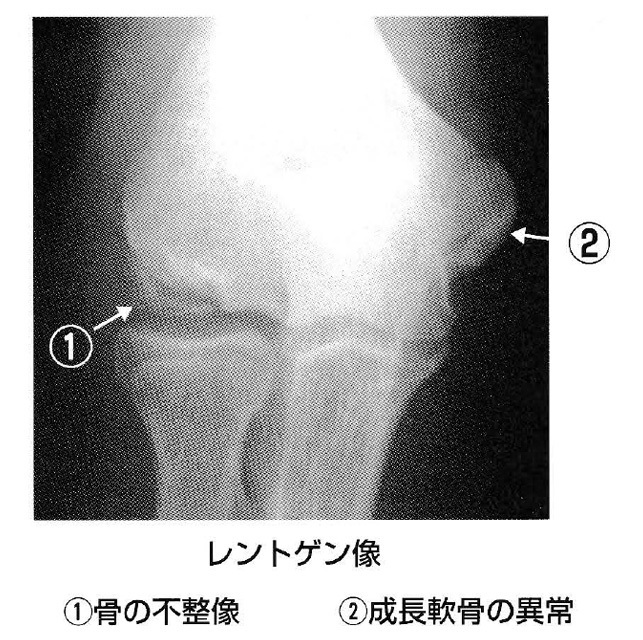

肘に痒みがあり動きも悪いなとの症状であれは、 野球肘が疑われます。レントゲン検査やMRI検査で診固します。

肘の外側では骨どうしがぶつかって骨と軟骨がはがれるこ ともあリます。肘の内側では靱帯や軟骨がいたみます。